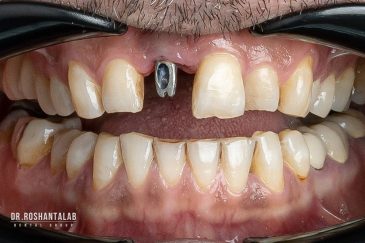

کلینیک تخصصی دکتر حسن روشن طلب با همکاری جمعی از متخصص ایمپلنت دندان و جراح فک و صورت بنام در حال فعالیت می باشد. این مجموعه مأموریت خود را ارائه خدمات تکمیلی دندانپزشکی در زمینه درمان های تخصصی و عمومی به شرح ذیل انجام می شود.

🔸 کاشت ایمپلنت دندان بدون درد

🔸کاشت ایمپلنت فلپ لس یا بدون جراحی و بدون بخیه زیر سه دقیقه

🔸 کاشت دندان یک روزه ( کشیدن و کاشت همزمان )

🔸 ایمپلنت دیجیتال و ساخت روکش دیجیتال